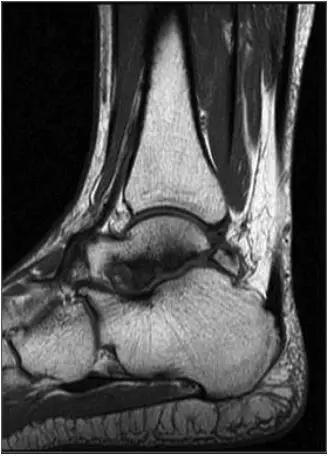

男,11岁,自述后踝下方疼痛,活动时为甚,并有一突起。

- 踝关节正侧位X 线平片,侧位片均显示距骨后方有三角形或椭圆形的距后三角骨。部分病例伴有轻度的踝关节骨性关节病。

- MRI 检查示距后三角骨及周围软组织有水肿信号,距后三角骨和距骨之间正常的低信号纤维连接中断,出现液性信号。

3、MR表现:

- 三角籽骨或距骨后三角结构模糊和变形,T1WI信号降低, T2WI信号升高,

- 周围脂肪水肿,

- 踇趾长屈肌腱信号升高,见鞘膜积液,

- 胫骨后下跟骨上缘骨结构形态变化和信号异常,

- 三角籽骨和距骨退行性囊变。